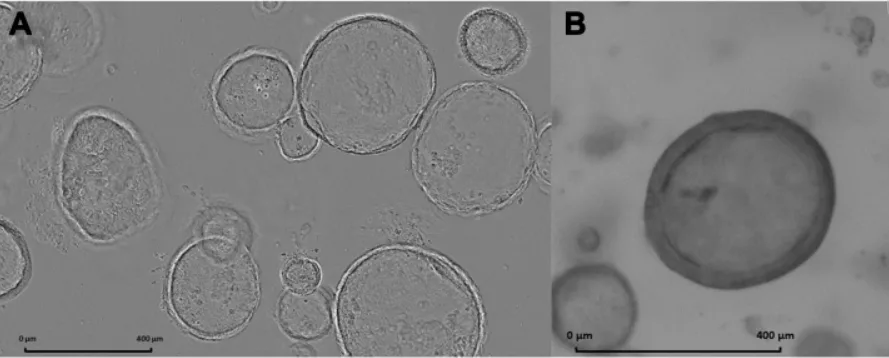

Customer Publication

23 Apr, 2021

Investigating Novel Treatment Options for Pancreatic Cancer

Roeth et al. (RWTH Aachen) explore Magnetic Fluid Hyperthermia as a novel therapeutic approach for pancreatic cancer. TissueFAXS and StrataQuest supported marker analysis of pancreatic cancer organoids in this innovative study.